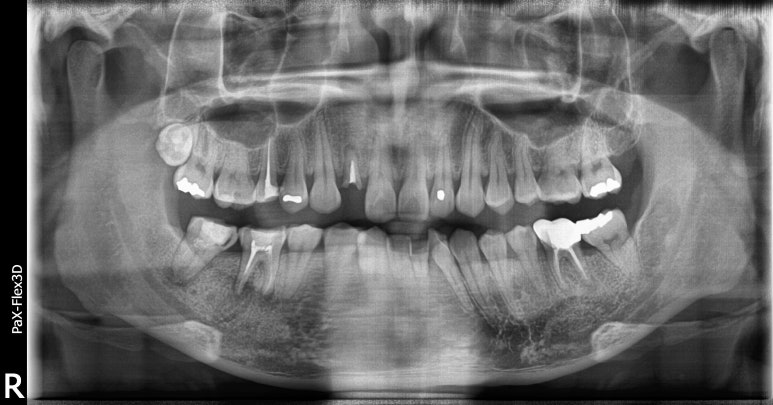

20대임플란트 실제 사례

28세 남성

(전) 2022-07-07 (후) 2022-09-02